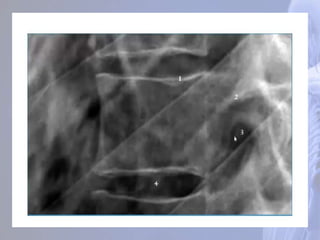

Articulação Costovertebral Fóveas Costais Superiore inferior Fóvea do Processo Transverso